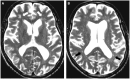

Mutations in the colony stimulating factor 1 receptor (CSF1R) have recently been discovered as causal for hereditary diffuse leukoencephalopathy with axonal spheroids. We identified a novel, heterozygous missense mutation in CSF1R [c.1990G > A p.(E664K)] by exome sequencing in five members of a family with hereditary diffuse leukoencephalopathy with axonal spheroids. Three affected siblings had characteristic white matter abnormalities and presented with progressive neurological decline. In the fourth affected sibling, early progression halted after allogeneic haematopoietic stem cell transplantation from a related donor. Blood spot DNA from this subject displayed chimerism in CSF1R acquired after haematopoietic stem cell transplantation. Interestingly, both parents were unaffected but the mother's blood and saliva were mosaic for the CSF1R mutation. Our findings suggest that expression of wild-type CSF1R in some cells, whether achieved by mosaicism or chimerism, may confer benefit in hereditary diffuse leukoencephalopathy with axonal spheroids and suggest that haematopoietic stem cell transplantation might have a therapeutic role for this disorder.